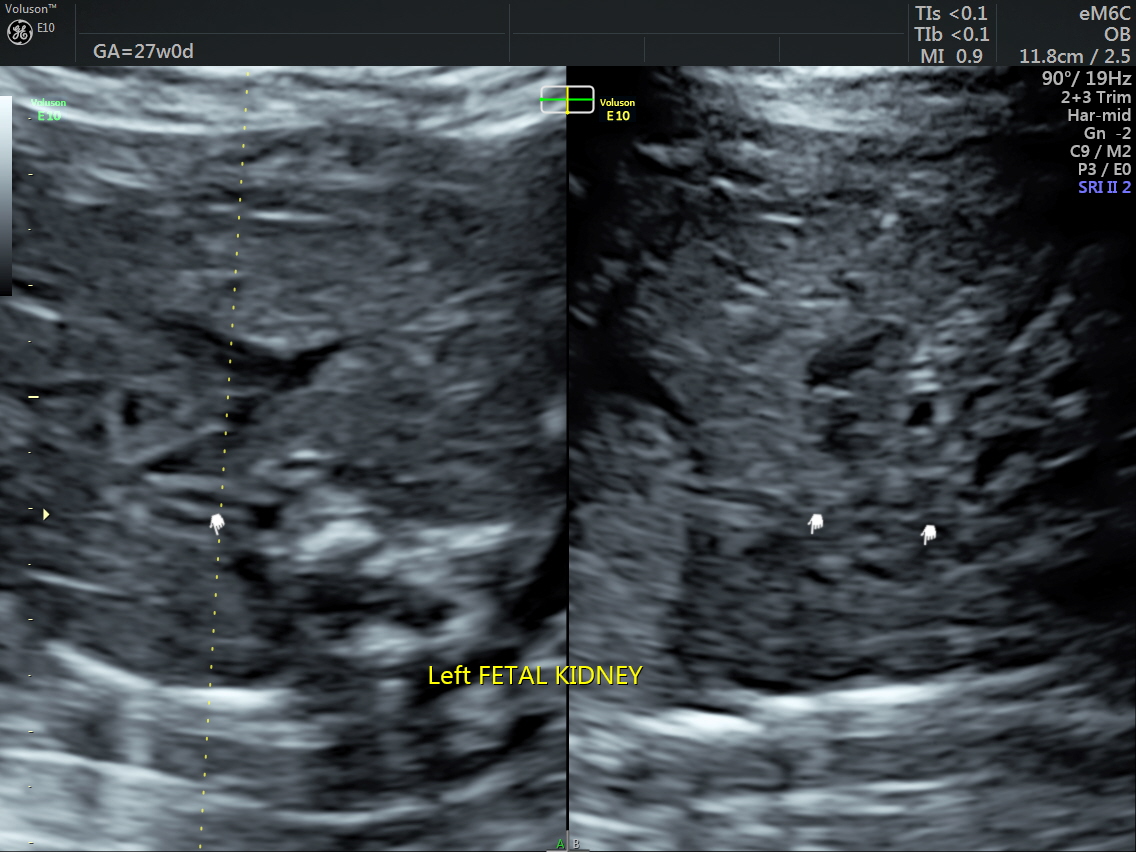

RT AORTIC ARCH_24 Published June 17, 2016 at 1136 × 852 in Rt aortic arch and aberrant left subclavian artery ← Previous Next →